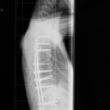

Scoliose